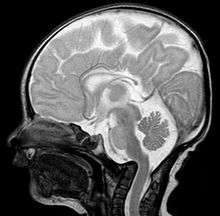

- Magnetic resonance imaging (MRI), which usually provides the most information